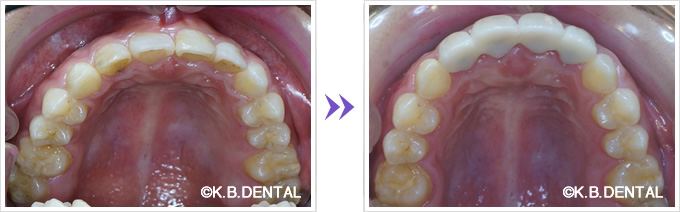

口蓋隆起 症例4(正中口蓋隆起)

口蓋の正中に発生した骨隆起です。静脈麻酔で約1時間半程度要します。

料金

静脈内鎮静法による麻酔代込み:約20万円(保険適用外)